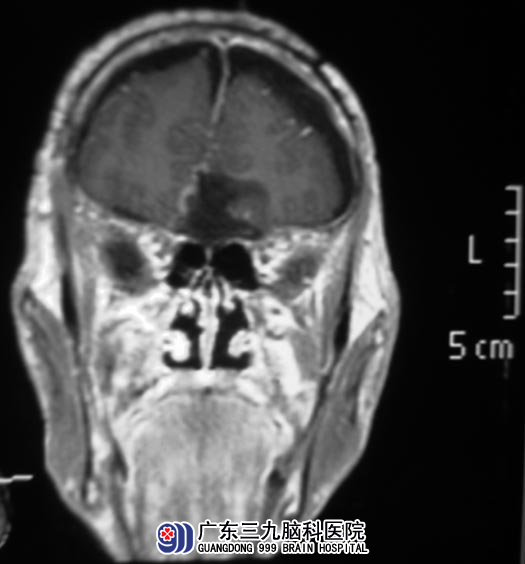

11月22日,鲁明主任主刀,在全麻下行经冠状入路嗅沟脑膜瘤切除术,显微镜下见肿瘤位于前颅窝底,呈肉红色,血供较丰富,自肿瘤基底部分离肿瘤,见肿瘤起源蝶骨嵴中内侧,嗅神经已经破坏,超声吸引器分块切除肿瘤,可见肿瘤后部分破坏前床突,上对大脑前动脉及双侧视神经有压迫,显微镜下予肿瘤全切除,视神经及大脑前动脉保护良好,手术顺利。术后病理结果为:过渡型脑膜瘤(WHO I 级)。

▲手术后